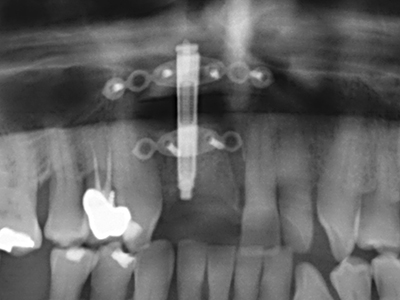

As shown in the past, basically any bone surgery procedure represents a possible indication for piezo surgery. Thus preparation of the mobile segment in distraction osteogenesis (Fig. 23-25) and sandwich osteotomy uses special attachments without endangering the blood supply to the crestal section, which is essential for the success of both techniques (Gonzalez-Garcia, Diniz-Freitas et al. 2008).

Purely orthodontic indications include orthognathic surgery, genioplasty (Fig. 27-30) and orbital decompression in patients with advanced endocrine orbitopathy as a result of Basedow’s disease (Ponto, Zwiener et al. 2014). Piezo devices are also used in maxillofacial surgery and to remove tumours at the base of the skull in various hospitals.